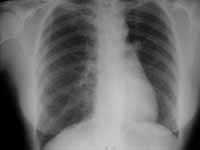

Así mismo en estas entidades de pulmón hiperlucente unilateral, se menciona el Síndrome de Swyer-James o Macleod, en el cual parece encontrarse como causa etiológica una bronquiolitis obliterativa que sigue a una neumonía viral por Adenovirus.(Figura 3).

Figura 3. Pulmón hiperlucente unilateral (Swyer-James).